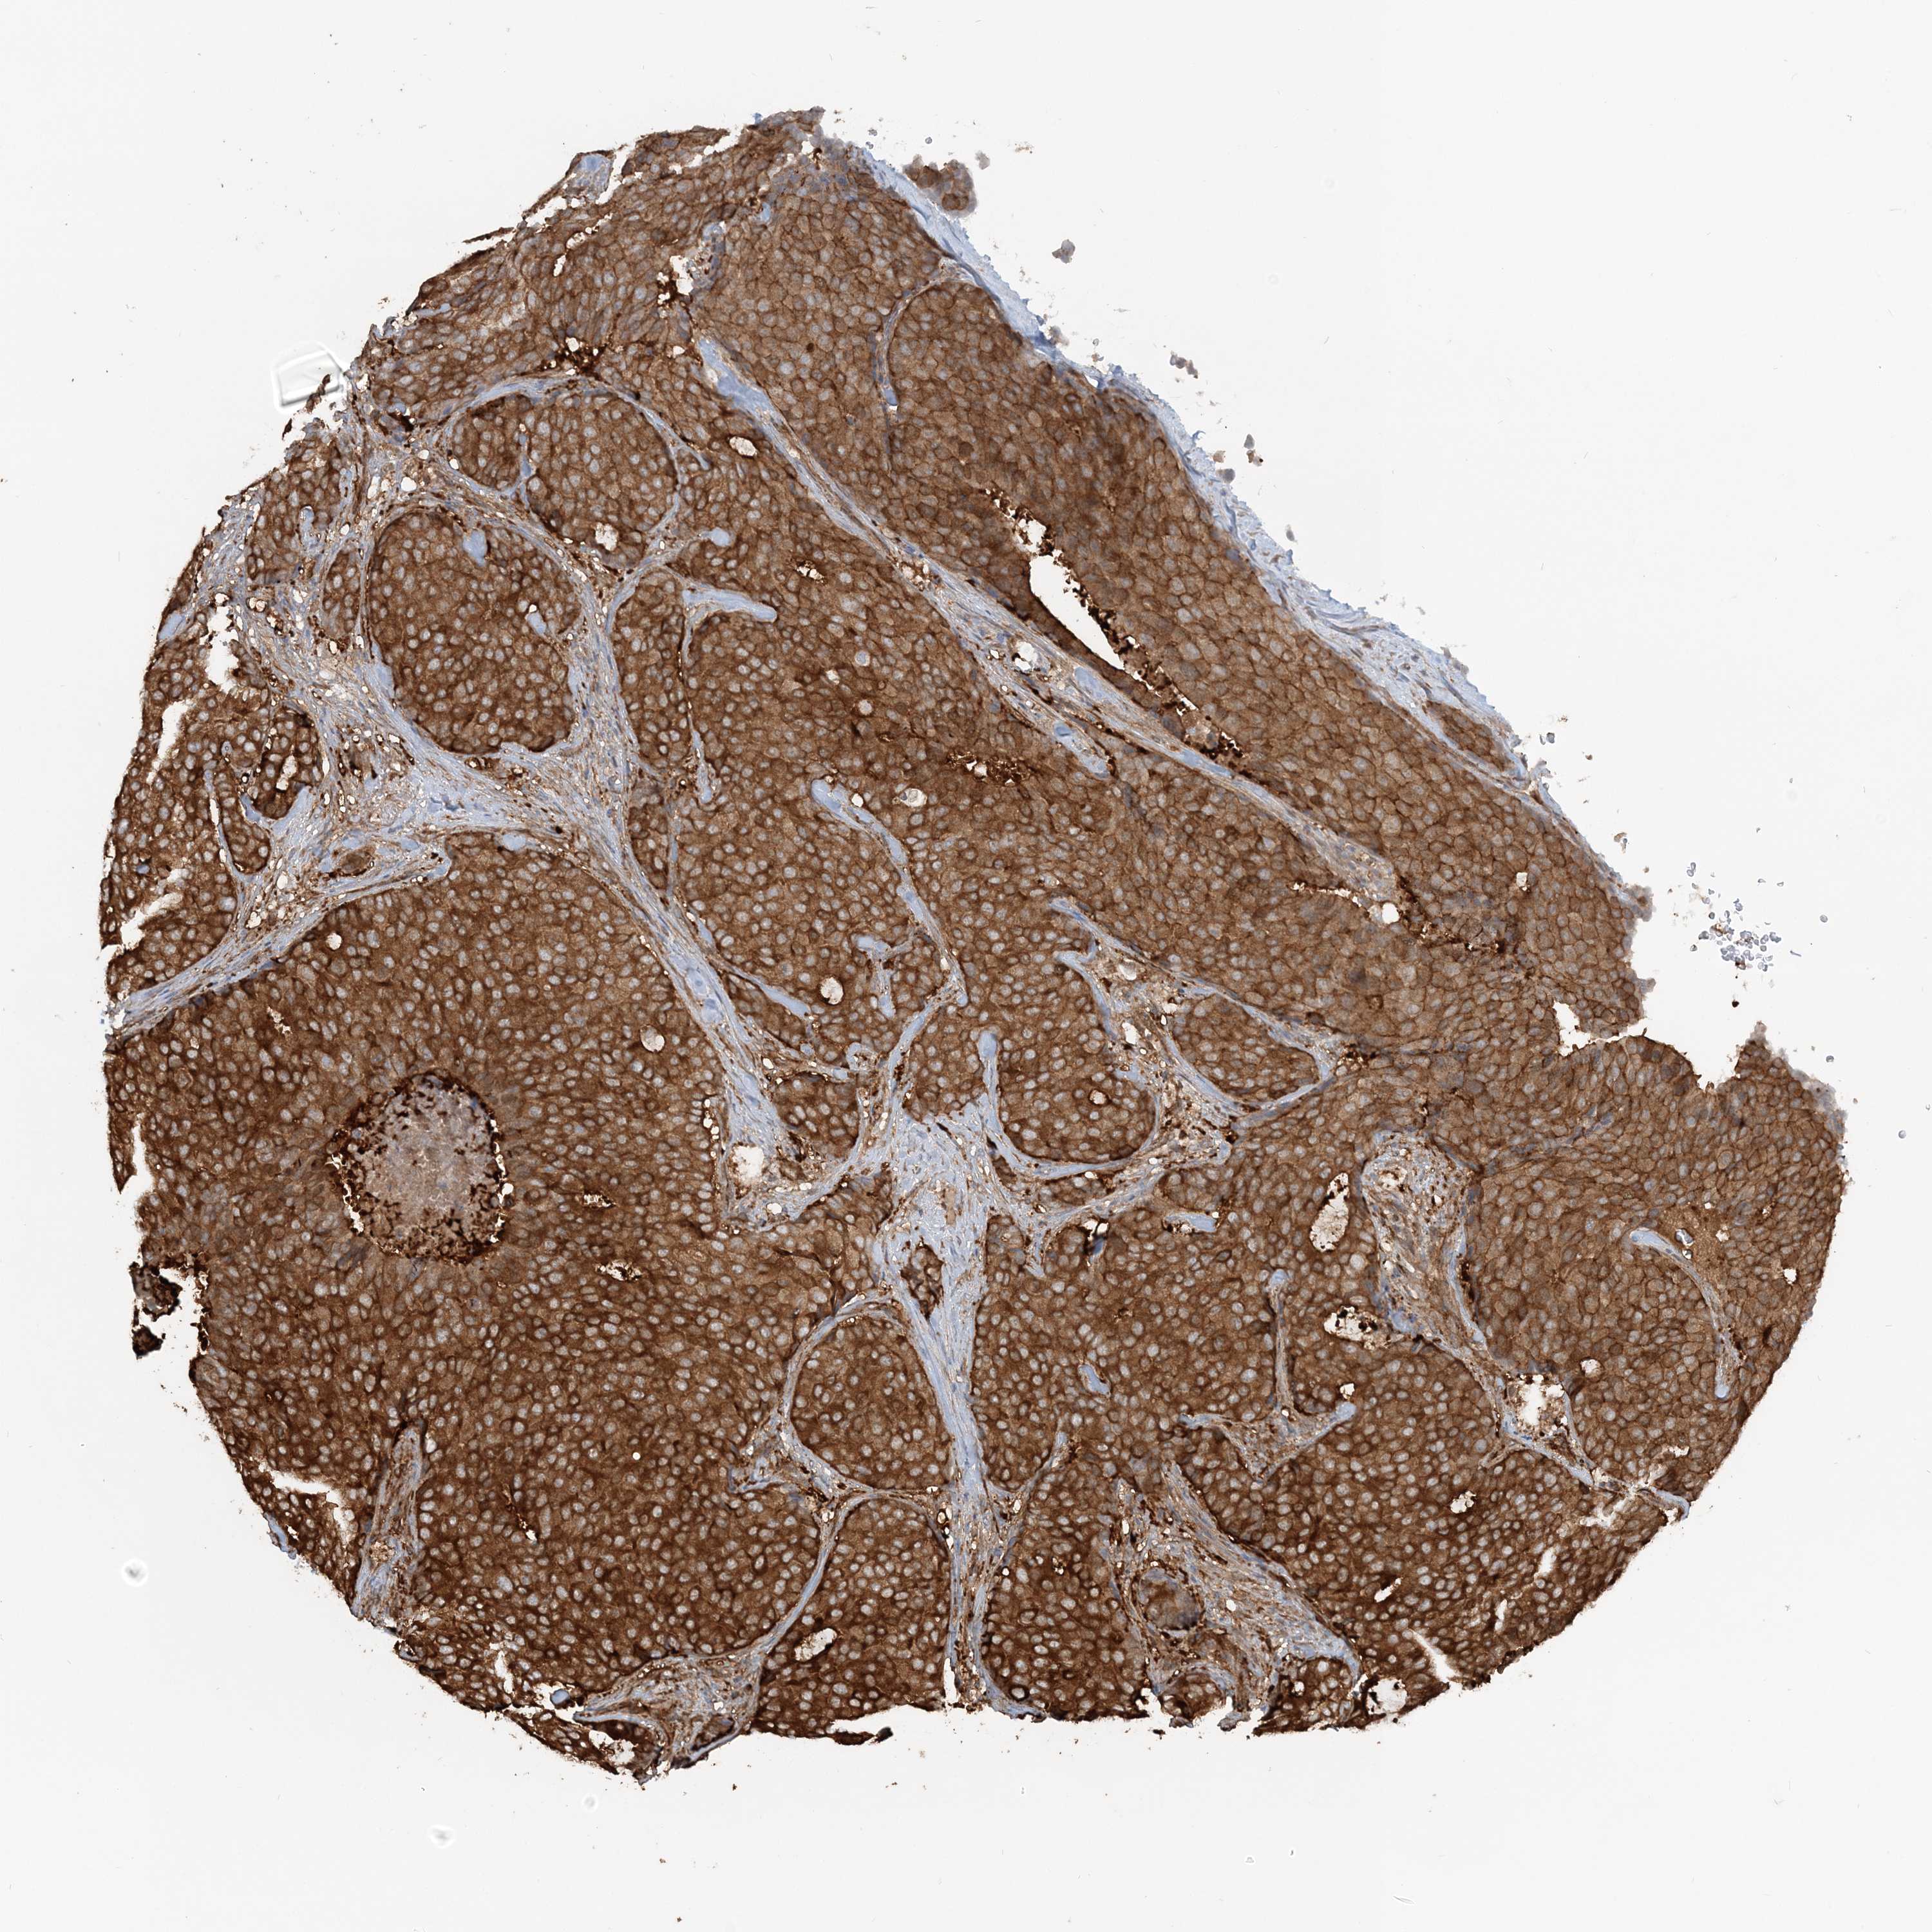

CANCER BREAST CANCER Show tissue menu

BRCA TCGA BRCA VALIDATION PROTEIN EXPRESSION